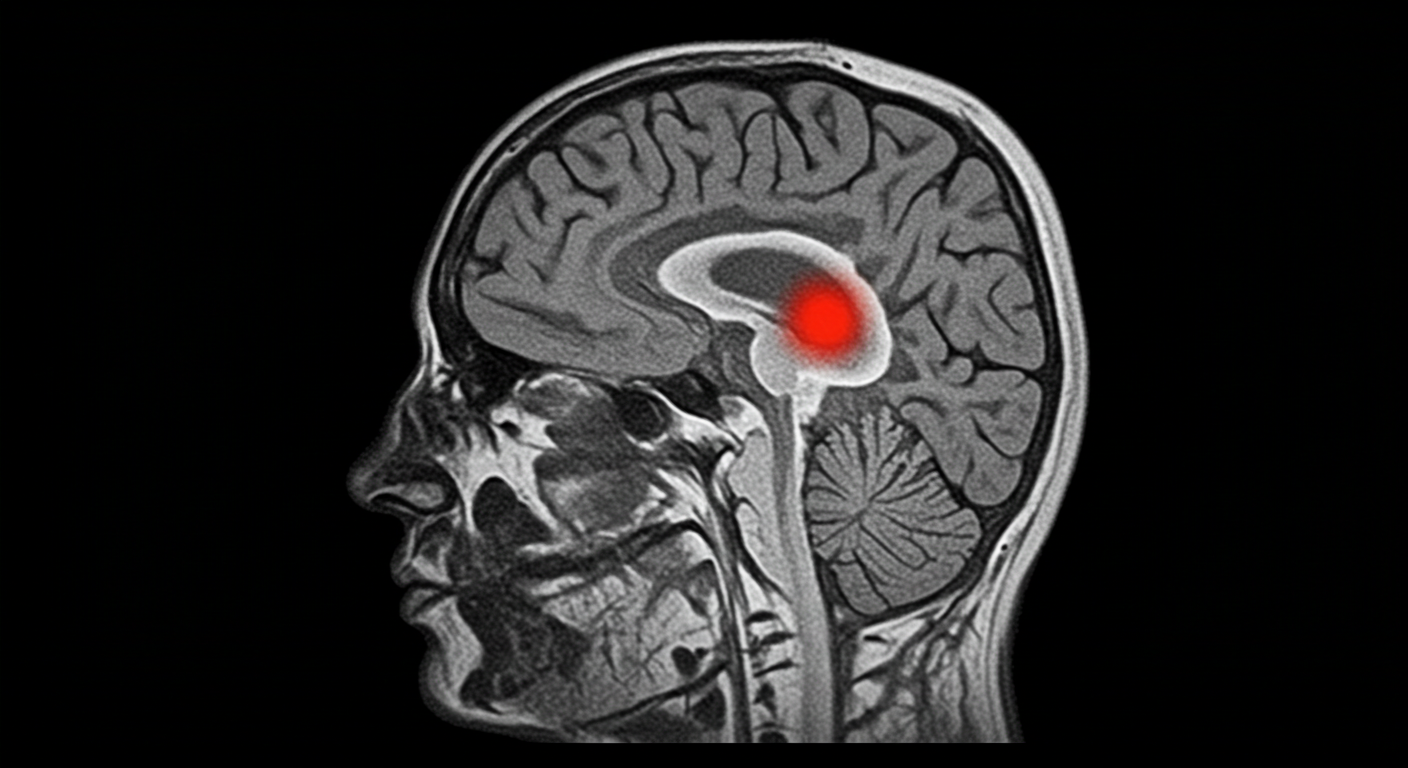

3. 뇌종양

뇌종양은 양성과 악성으로 나뉘며, 조기 발견 시 수술적 치료나 방사선 치료로 완치 가능성이 높습니다. 특히 초기에는 증상이 거의 없어 정기적인 검진이 중요합니다.